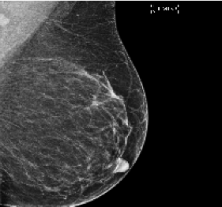

NVFlare and its predecessors have been used in several real-world studies exploring FL for healthcare scenarios. The collaborations between multinational institutions tested and validated the utility of federated learning, pushing the envelope for training robust, generalizable AI models. These initiatives included FL for breast mammography classification [32], prostate segmentation [33], pancreas segmentation [37], and most recently, chest X-ray (CXR) and electronic health record (EHR) analysis to predict the oxygen requirement for patients arriving in the emergency department with symptoms of COVID-19 [6].